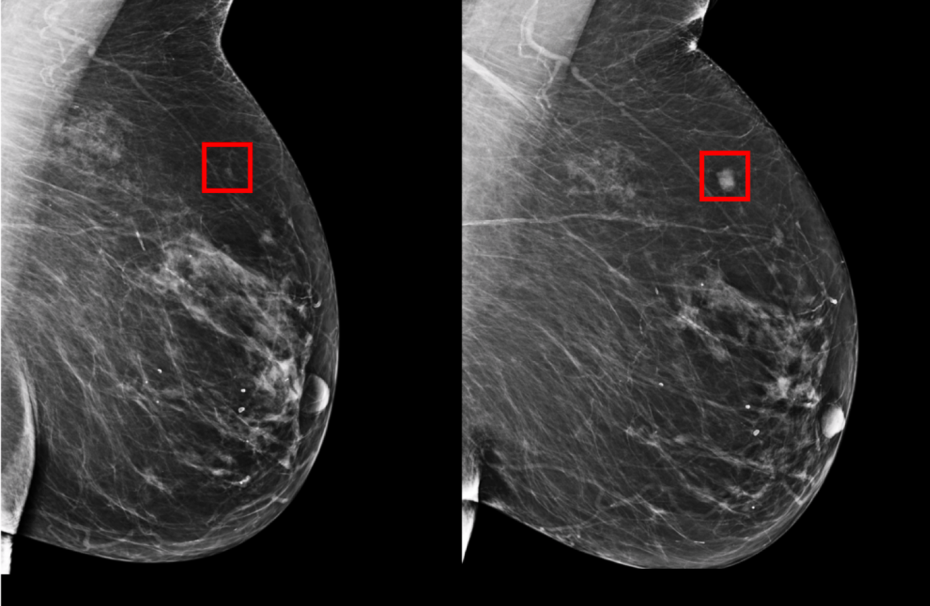

В качестве первичного диагностического исследования врачи используют маммографию. Это рентгенографическая процедура, позволяющая обнаружить патологические изменения на ранней стадии. До 90 % опухолей выявляются этим способом. Сейчас широко применяется цифровая маммография, которая дает возможность увеличивать изображение, делать его более ярким или контрастным, пересылать по интернету для онлайн-консультации. Этот диагностический метод позволяет обнаружить новообразования, оценить их структуру, но дополнительные сведения можно получить только с помощью других исследований.

Также онкологи проводят ультразвуковое исследование. Этот метод обладает особенно высокой информативностью при выявлении признаков онкозаболеваний молочных желез у молодых женщин за счет того, что плотность тканей у них более высокая. Его также используют, чтобы проконтролировать результаты биопсии.

Магнитно-резонансную томографию (МРТ) молочных желез применяют, если нужно уточнить результаты, полученные с помощью других методов диагностики. МРТ дает возможность определить размеры образования, точно локализовать его: без этой информации нельзя проводить хирургическое вмешательство.